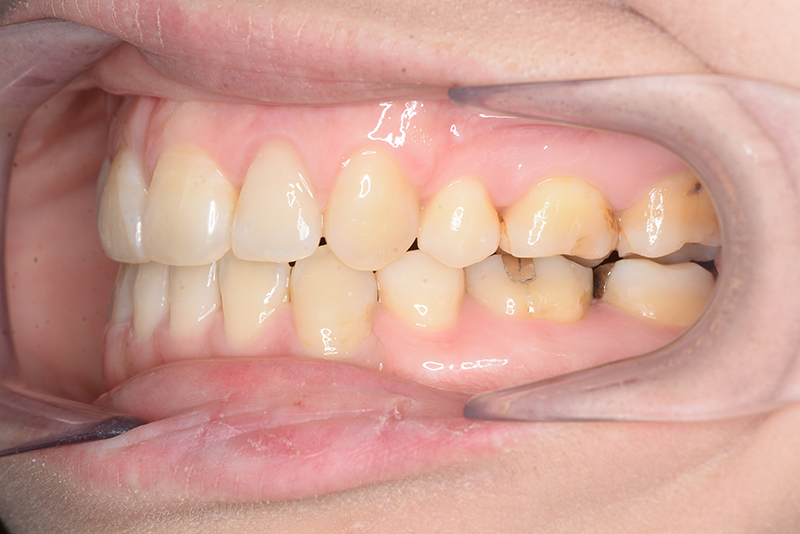

| 口腔内所見 | 臼歯関係はⅠ級、over jet 4.5mm、over bite -3.0mm。上下顎切歯部に軽度の叢生が認められ唇側傾斜をしつつ開咬を呈していた。 |

| 批評・予后 | 治療後において下顎角の開大も認められず歯軸の整直、咬合の緊密化が得られた。また上下顎前歯の後退と共に口元の突出感と口唇閉鎖不全の改善が認められた。 |